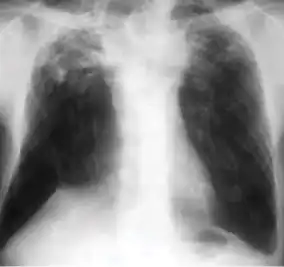

Chest x-ray showing bilateral hilar adenopathy of primary pulmonary TB